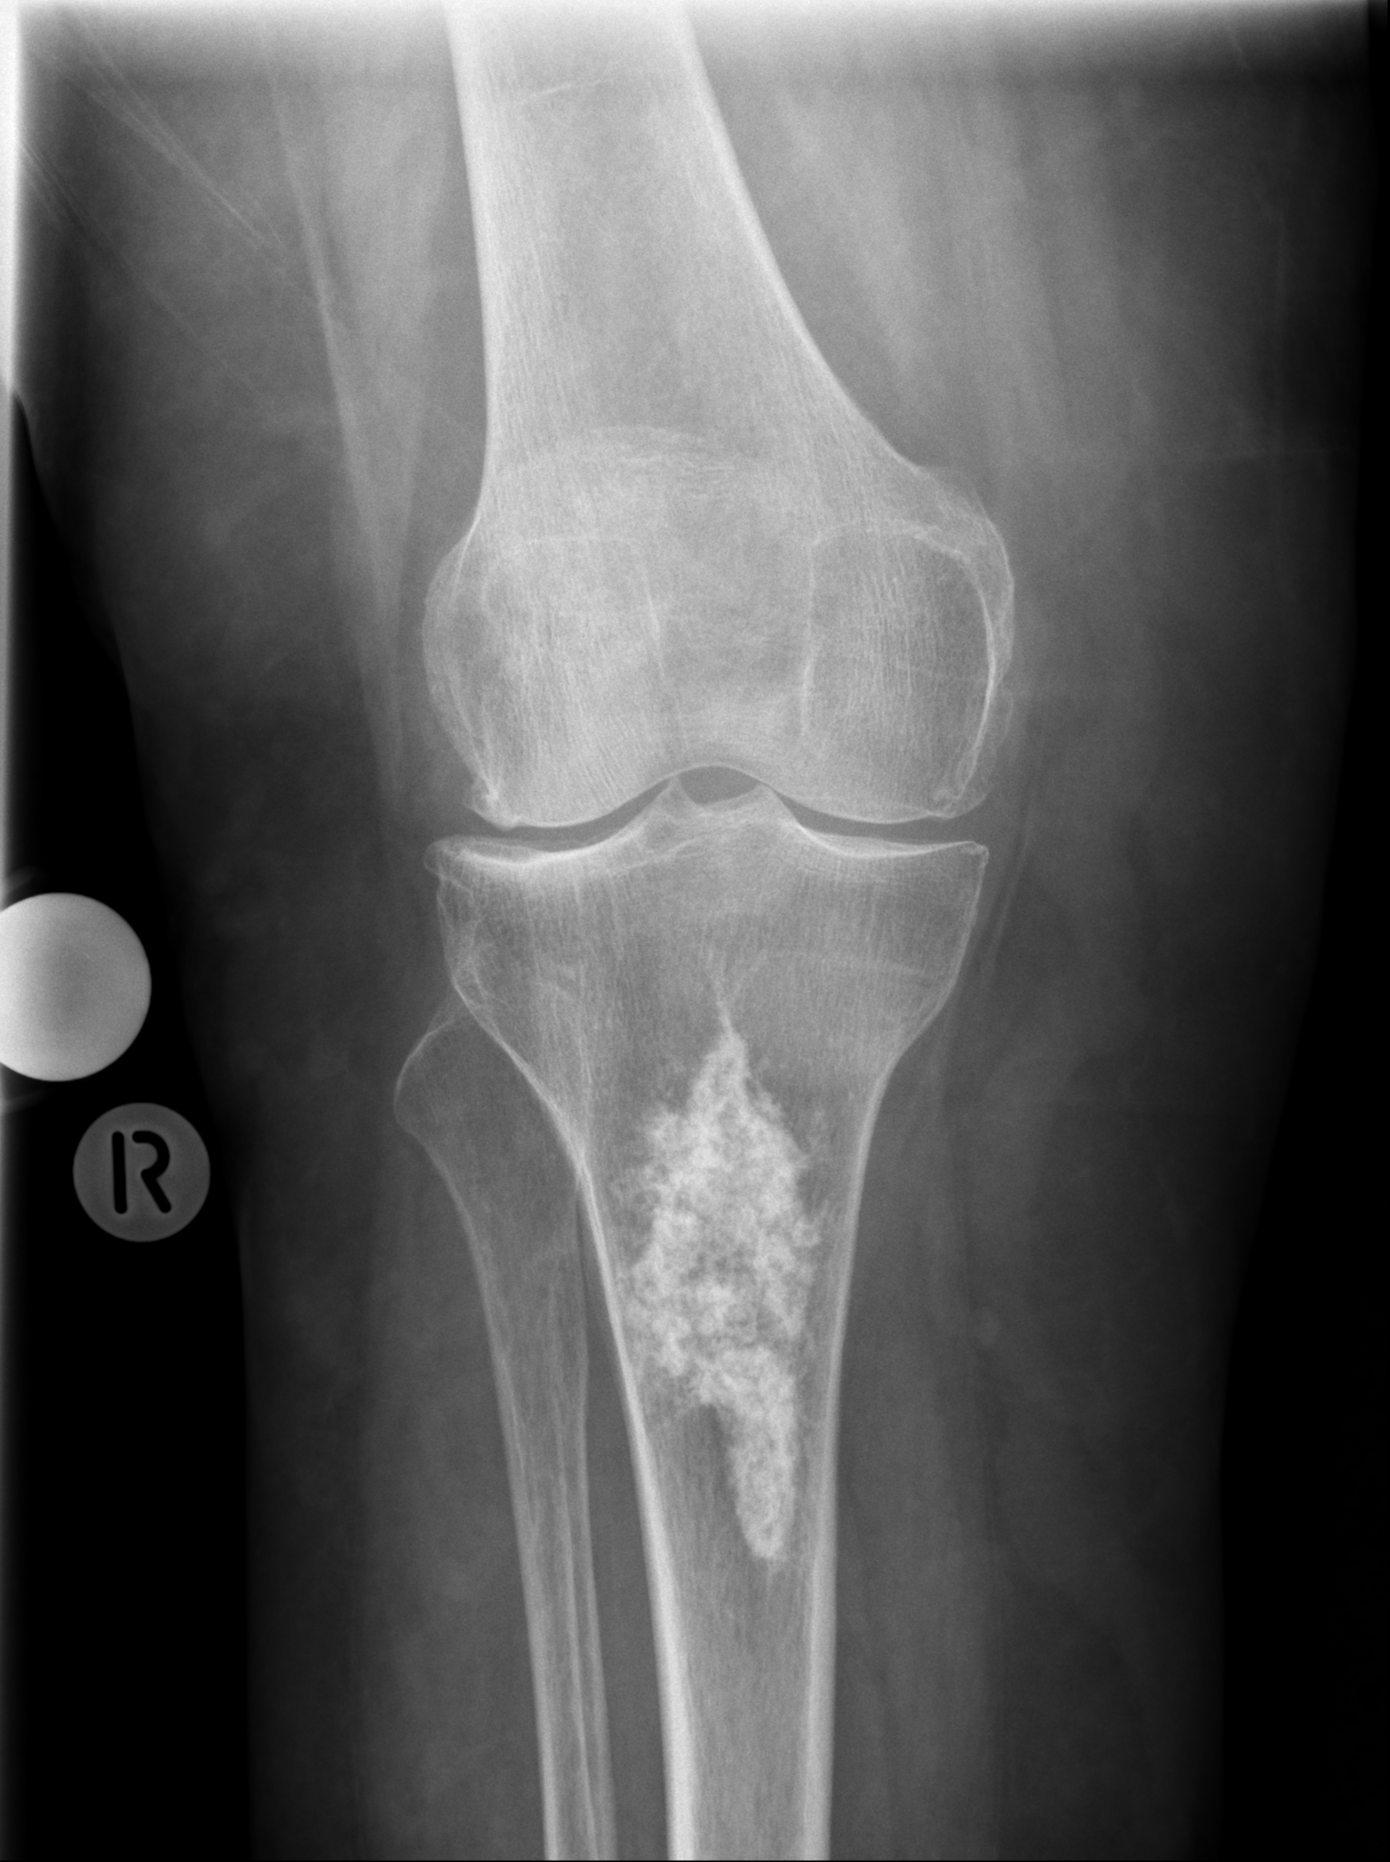

Worum handelt es sich bei der Läsion in der proximalen Tibia am ehesten? Demographische Daten: 75-jährige Patientin.